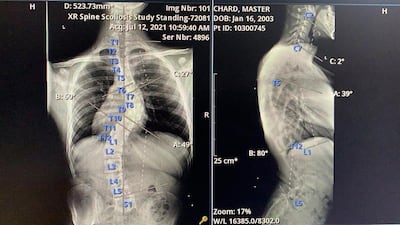

Despite having an S-shaped spine with a severe 47° curvature, Mr Chard has avoided 12-hour realignment surgery and the need for a corrective brace, largely thanks to the thousands of hours spent training on the water since childhood.

Convex curves to the right are more common, while C-curves or S-curves as in the case of Mr Chard are more unusual.